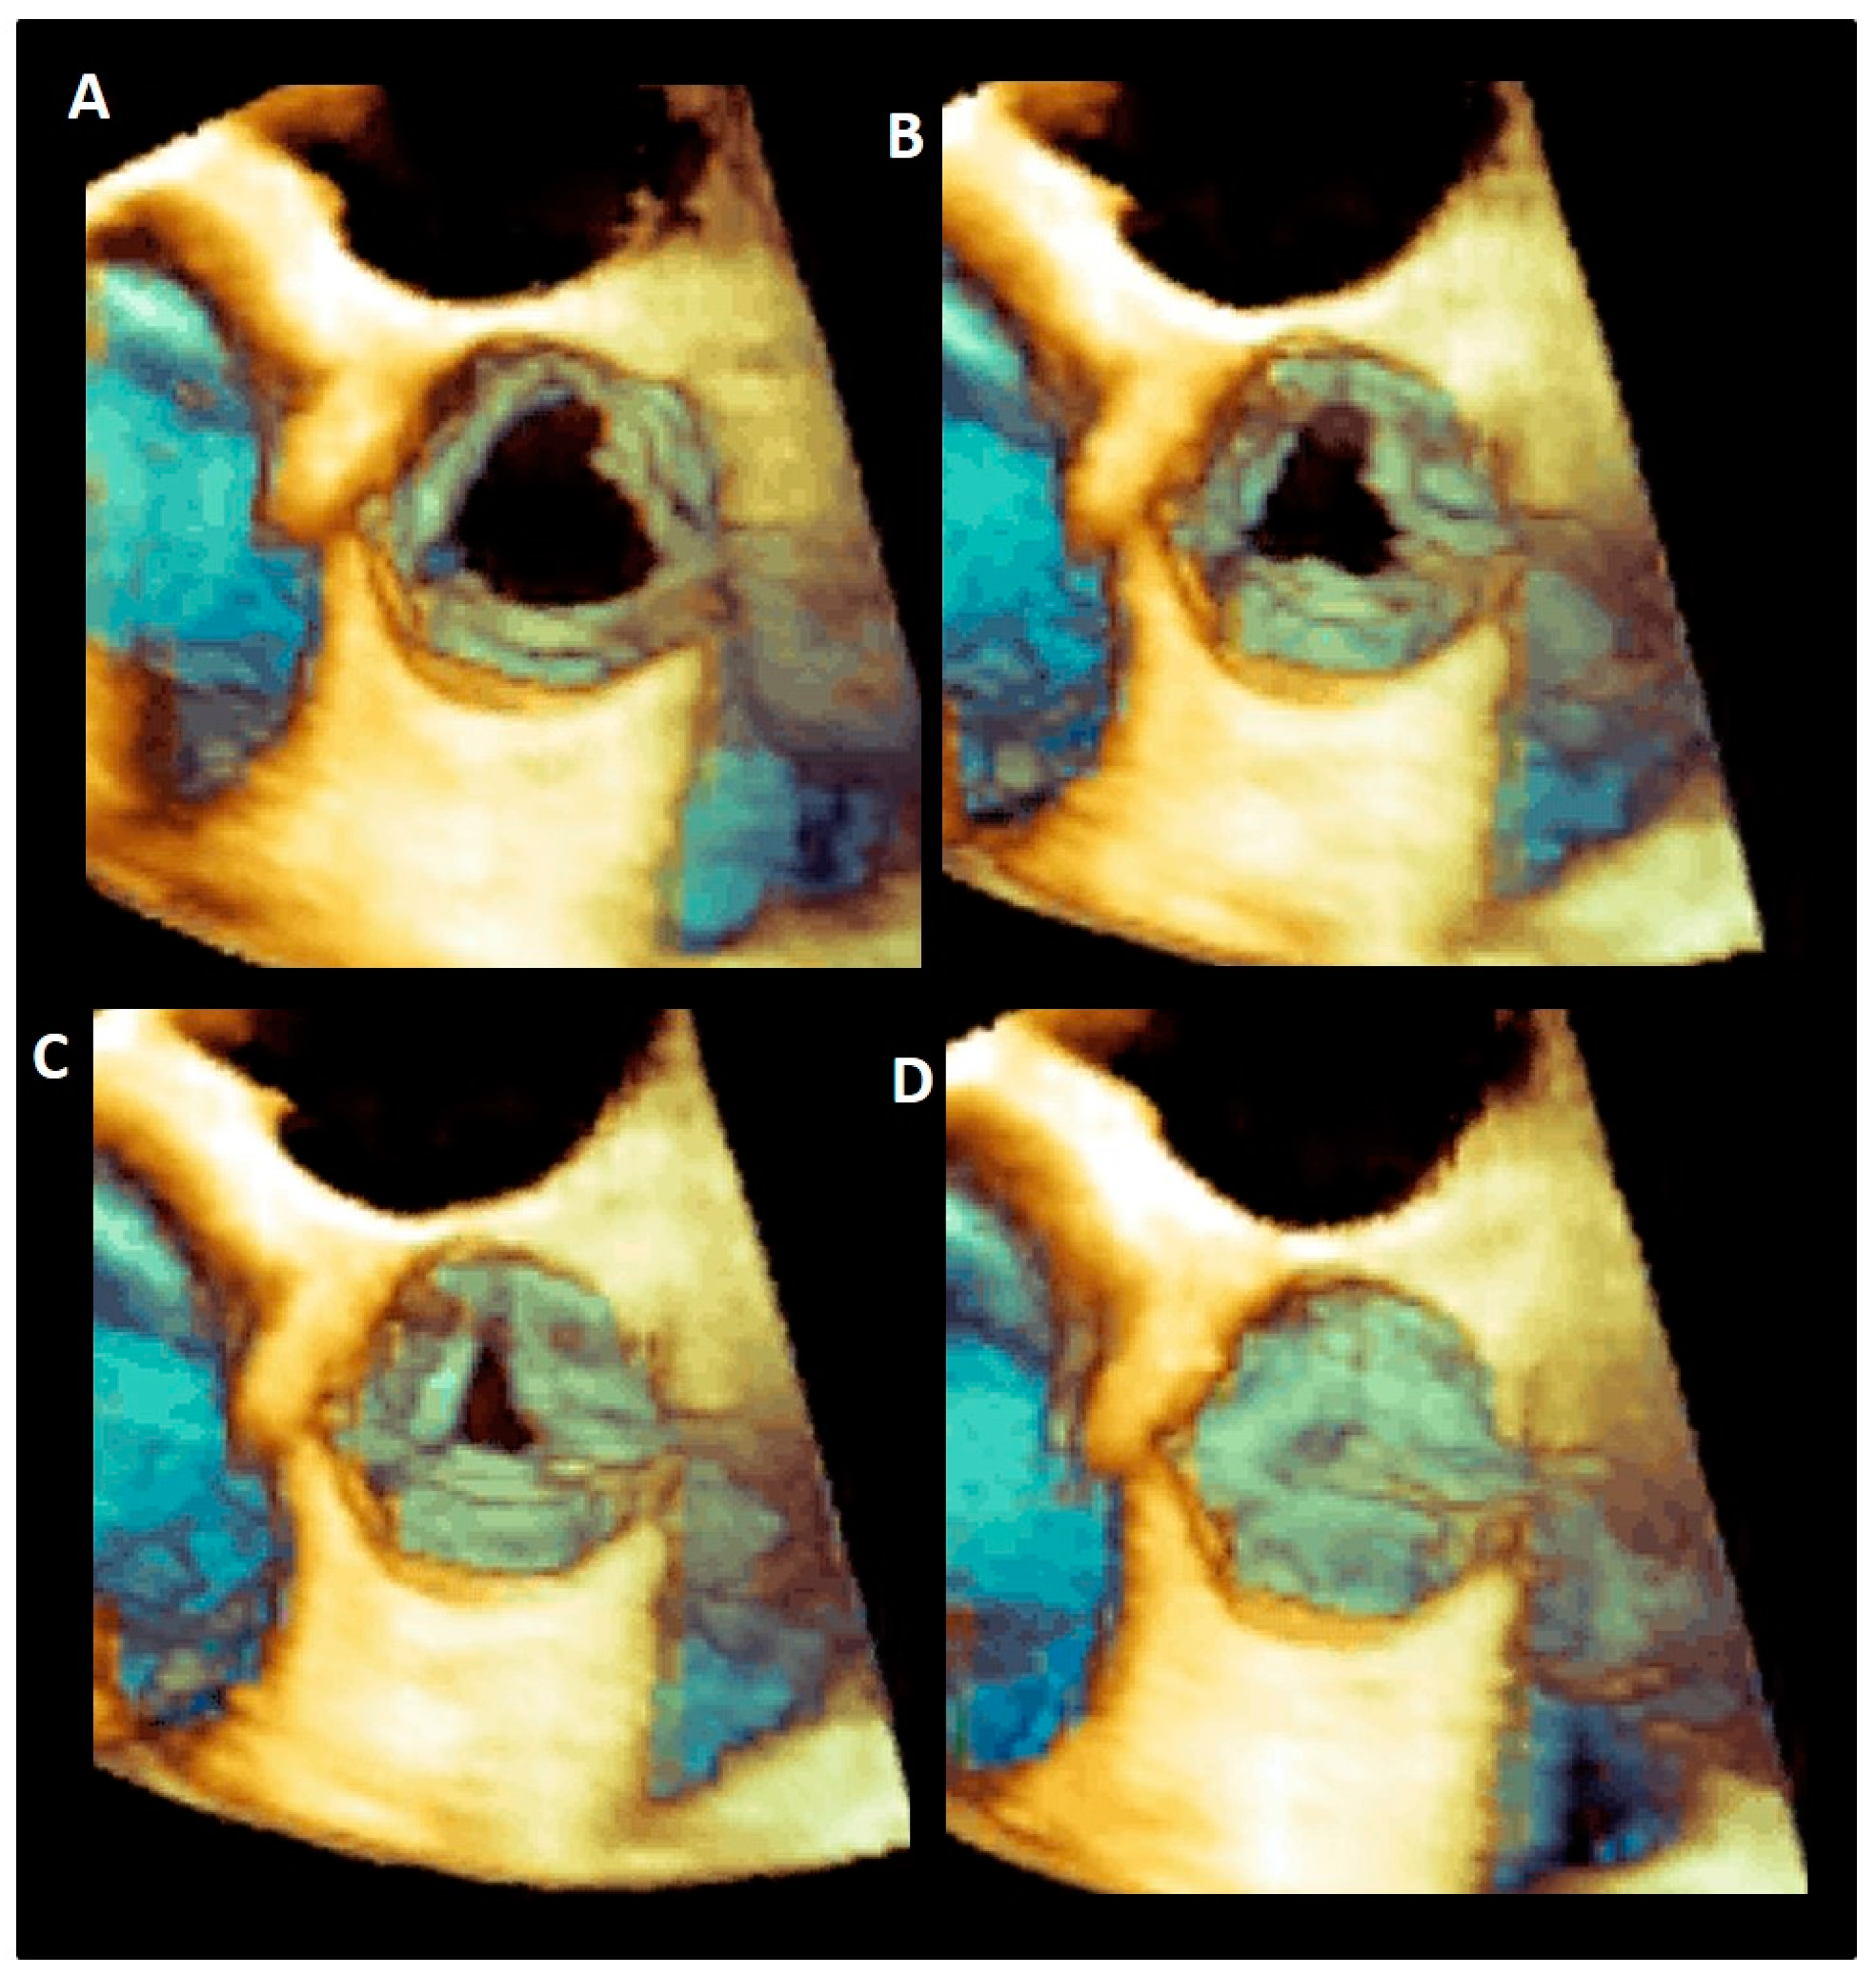

| Cusps, leaflets | The term “cusps” refers to the moving parts of the aortic root. When seen in closed position from the ventricular perspective, this component is similar to the surface of a molar tooth (called cusp). The term is used to describe the structure of the valve (i.e., unicuspidal, bicuspid, and tri-cuspid). Literally the term indicates a pointed end where two curves meet. In the aortic root, it indicates an intact interleaflet triangle with its apex reaching the sinutubular junction. The term leaflet means “small leaf”, which describes a thin, pliable layer. This term perfectly fits the leaflet aspect. N = non-coronary, L = left coronary, R = right coronary leaflets/cusps. | ![]() |